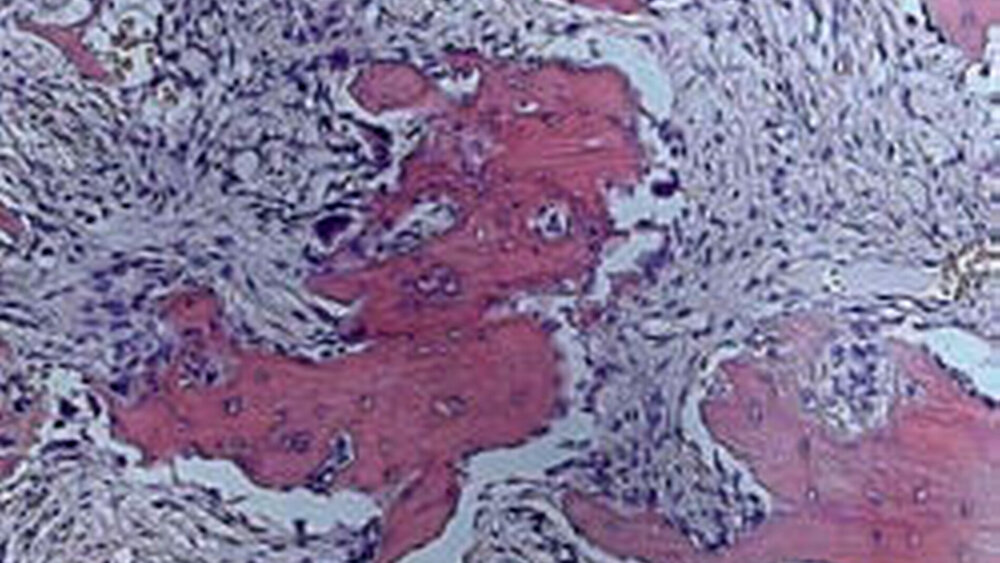

Da Rezidive bei Osteomen in der Regel nicht vorkommen [Neville, 2002], wurde eine Exzisionsbiopsie der Knochenveränderung bei der Patientin durchgeführt. Intraoperativ ließ sich der Befund nur schwierig vom umgebenden Knochengewebe abgrenzen. Die histologische Untersuchung zeigte zementtypische, plattenartig konfigurierte Hartsubstanzablagerungen, die mit ortsständigem, im Umbau befindlichem Knochen teilweise fusionierten, welches zur Diagnose einer so genannten fokalen zemento-ossären Dysplasie führte.

Die fokale zemento-ossäre Dysplasie (Synonyme: periapikale Zementdysplasie, periapikales Osteofibrom, periapikale fibröse Dysplasie, periapikales Fibro-Osteom, periapikales Fibro-Osteo-Zementom, Zementom, Fibrozementom, sklerosierendes Zementom) [Reichart, 2004] stellt eine nicht neoplastische knochenassoziierte Läsion des Kiefers dar, die ihren Ursprung wahrscheinlich im periodontalen Ligament hat [Reichart, 2004; Kawai, 1999]. Ihr Verbindungsglied schienen bisher unterschiedlich stark ausgeprägte Zementablagerungen mit relativ typischem Röntgenbefund zu sein (Abbildung 1). Die neue WHO-Klassifikation der Kopf-Hals-Tumoren vereinfacht die mannigfaltige Nomenklatur, indem sie diese Entitäten unter dem Begriff Ossäre Dysplasie (OD) zusammenfasst [Slootweg, 2005]. Die jahrzehntelange Diskussion zur Frage, ob Zement vorliegt oder nicht, wurde hiermit in vereinfachender Weise geklärt [Reichart, 2006]. Ihre Ätiologie ist größtenteils unbekannt [Jundt, 1997], ein traumatisches Ereignis, wie eine vorausgegangene Zahnentfernung, wird diskutiert [Waal, 1993]. Im vorliegenden Fall war der linke untere Weisheitszahn etwa zwanzig Jahre zuvor entfernt worden.